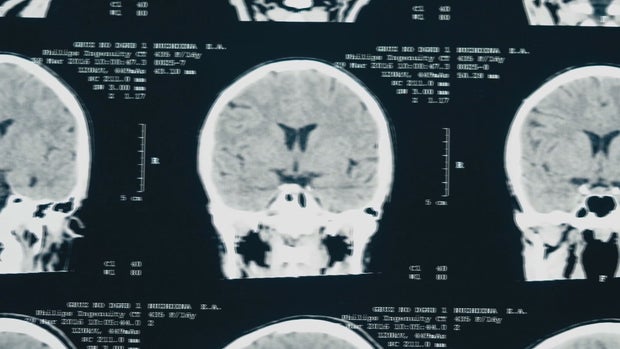

"What stood out to me was… the term unlucky- to hit your head in just that one spot because with this type of an injury, it's called an epidural hematoma, so you cut an artery on sort of the covering of the brain and you have to be very specific where you get hit for that to happen," said Dr. Kathryn Beauchamp a Neurosurgeon with Denver Health.

From the paramedics to the physicians looking at her CT scan, not a second was wasted. She was in and out of surgery in under 20 minutes.